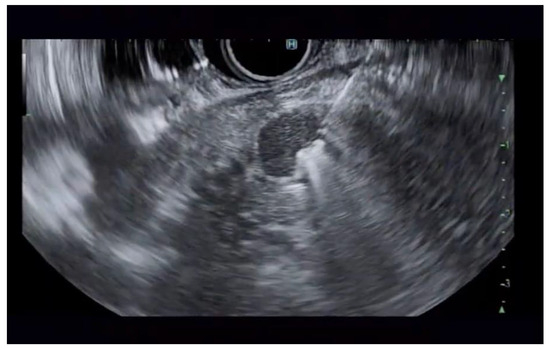

Additional notable cases in our series included a pancreatic cyst with a high-grade dysplastic nodule in an 80-year-old female patient. The initial 11.0 × 10.0 mm nodule was completely ablated (0.0 × 0.0 mm residual) after a single RFA session using a 19-gauge/7 mm needle at 50 watts of power for three applications with no complications (Figure 1, Figure 2 and Figure 3). Similarly, a 41-year-old male with a 13.5 × 8.5 mm insulinoma in the pancreatic neck who presented with multiple syncopal episodes secondary to hypoglycemia achieved complete radiologic and biochemical resolution after a single RFA session using a 19-gauge/5 mm needle at 10 watts of power for two applications (Figure 4, Figure 5 and Figure 6), with no adverse events and normalization of his insulin and glucose levels post-procedure and the resolution of his syncope.

Figure 1. Pancreatic cyst with mural nodule and high-grade dysplasia on EUS.